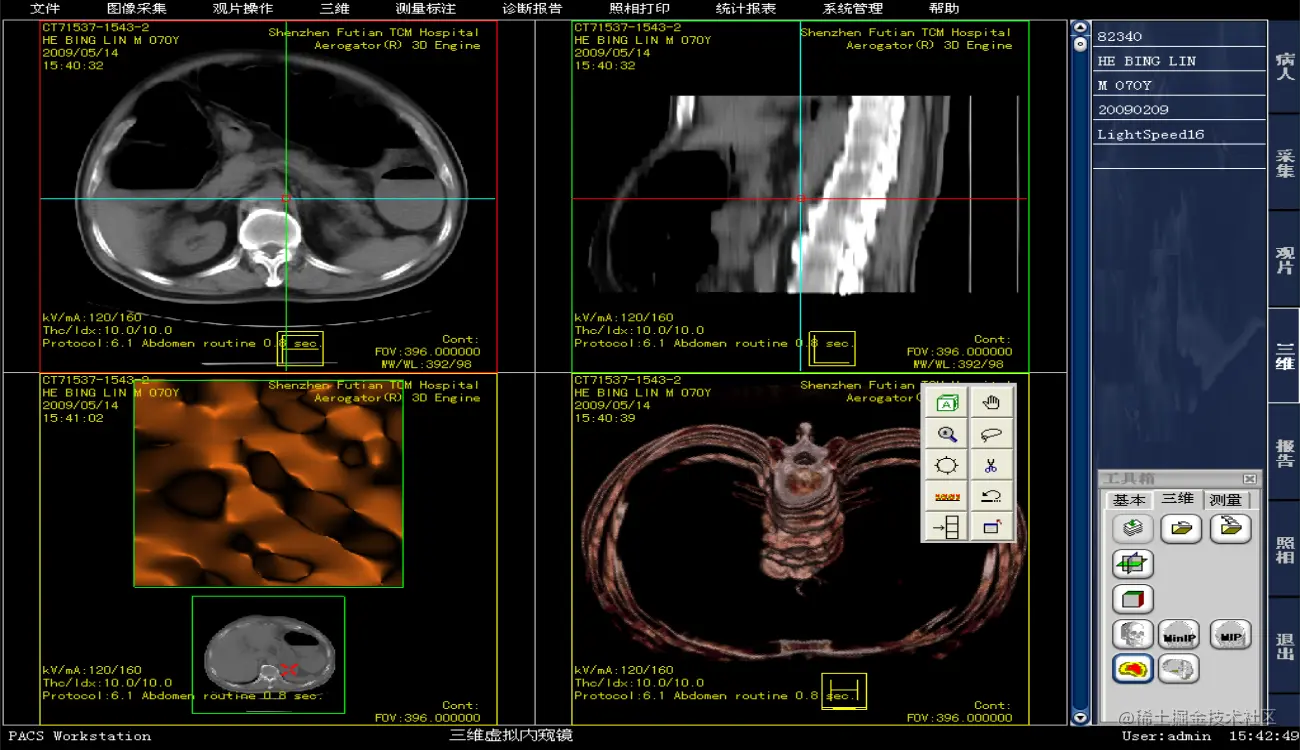

PACS系统源码,带3D重建PACS源码

完全符合DICOM3.0标准,显示各种类型影像,如:CR、DR、CT、MRI、DSA、RF、US、OT等;可显示播放DICOM多帧各种动态影像。

支持MPR、MIP、SSD等三维后处理功能。

三维模式:可以对图像进行三维后处理,如MPR、MIP、SSD等处理。